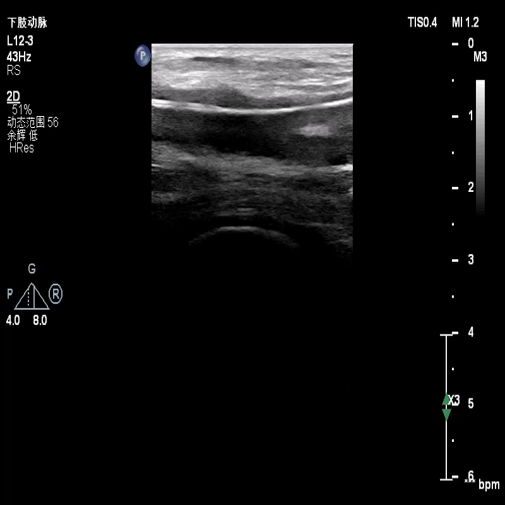

图:术前超声

手术操作:系统溶栓治疗3天,症状未缓解,考虑其血栓时间较长,超声引导下行右髂动脉覆膜支架置入术

图:超声引导髂动脉覆膜支架置入术

图:髂动脉支架置入术后